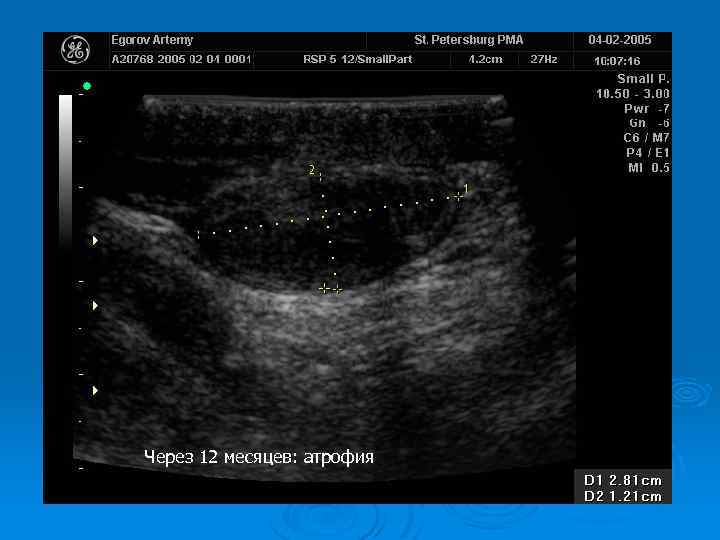

Через 12 месяцев: атрофия

Перекрут яичка: наблюдение в динамике Ø Регулярный УЗИ контроль Ø Оценка гормонального статуса Ø Исследование эякулята